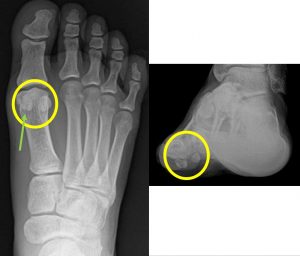

엄지발가락통증의 원인을 찾기위해 의사는 간단한 검사와 함께 생활 습관이나 최근 부상등에 대해 물어볼것입니다.

그리고 엄지발가락을 위아래로 구부려보고 뼈 박차와 부종이 있는지 확인할 것입니다.

필요에 따라서는 x-ray를 이용할 수도 있습니다. 통증의 원인에 따라 추가 검사가 필요할수도 있습니다.